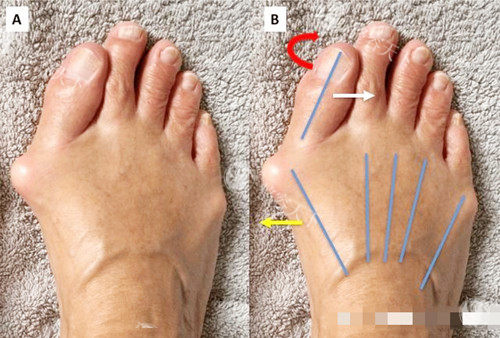

“温主任,我这脚能不开刀吗?”28岁的模特小夏捂着脚,眼里闪着泪光。温建民笑着拿起模型:“咱们用‘温氏微创法’,局麻,切口1厘米,术后当天就能下地。”

这位我国中医科学院望京医院的骨科主任,可是拇外翻微创界的“泰斗”——30年前就首创“手法复位+小夹板固定”,后来迭代成“1厘米微切口+可吸收线缝合”,获国家科技进步二等奖,治疗好6万多例患者,连德国发明展都给他颁了金奖!

患者实录:56岁的刘阿姨术后两周发朋友圈:“以前穿凉鞋像‘螃蟹出洞’,现在脚型自然,跳广场舞都不疼!”温建民的“杀手锏”是中医裹帘固定,避免二次手术取钢钉,术后5年复发率仅2.7%。

但微创也有“软肋”:对重度畸形(拇外翻角>40度)结果有限,患者术后得管住嘴——穿高跟鞋、久站都可能让骨头“反弹”。温建民团队为此设计“术后改善包”,包含定制足弓垫和运动指导,把复发风险再降一成。

切口大小:1厘米VS3厘米,小创口完胜?

温建民的1厘米切口像“针眼”,术后不用拆线,夏天穿凉鞋无压力;李昕宇的3-5厘米切口虽长,但能直视骨骼,对复杂畸形更“稳”。